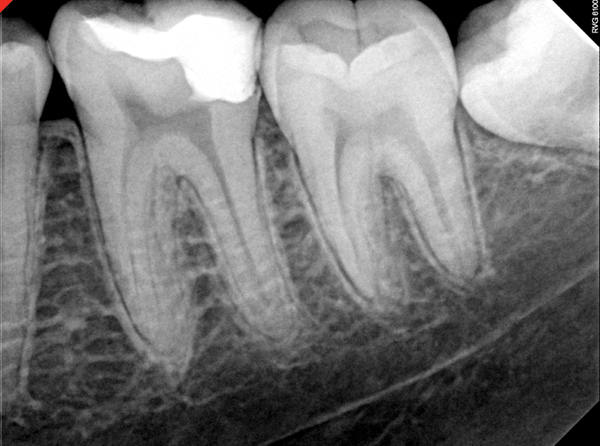

Figure 4. AND Figure 5. Before and after radiographs of bioceramic sealer hydraulically moved with the gutta-percha point. Note that the cold hydraulic technique results in lateral canal “puffs” similar to the warm vertical technique. Courtesy of Dr. Mohammed A. Alharbi.

Figure 4

Figure 5

Pre-mixed BC Sealer is the only pure medical-grade bioceramic product available as a sealer for endodontic obturation. It has the same basic chemical composition as the other pre-mixed bioceramic products, but it is less viscous, which makes its consistency ideal for sealing root canals. It is used with a gutta-percha point, which is impregnated on the surface with a nano particle layer of bioceramic. The gutta-percha is used primarily as the delivery device (plugger) (Figure 1 through Figure 3) to allow hydraulic movement of the sealer into the irregularities of the root canal and accessory canals (Figure 4 and Figure 5).